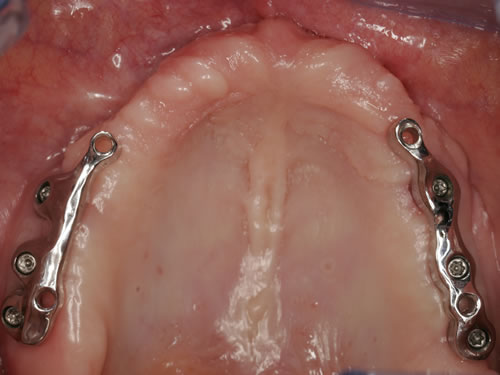

Diese Beispiele ließen sich endlos fortführen. Sie zeigen die Probleme bei der Versorgung zahnloser Kiefer, wie sie immer wieder geschildert werden. Mit Hilfe sehr einfacher Maßnahmen kann durch die Einpflanzung künstlicher Zahnwurzeln eine instabile Prothese soweit befestigt werden, dass die Kau- und Sprechfunktion wieder hergestellt ist. Manchmal kann die alte Prothese weiterverwendet werden, in dem man in die Prothesenbasis Sekundärteile einarbeitet, die für Halt sorgen (Abb. 3.5, 3.6). Bei aufwendigeren Steg- oder Teleskoparbeiten muss auch der Zahnersatz der auf den Implantaten fixiert wird neu angefertigt werden. Diese Arbeiten werden dann brückenartig und sehr grazil gestaltet. (Abb. 3.7 bis 3.12).

Abb. 3.7: Individuelle Stegversorgung aus Stahl auf vier Implantaten im zahnlosen Unterkiefer.

Abb. 3.8: Individuelle Stegversorgung aus Gold auf vier Implantaten im zahnlosen Unterkiefer.

Abb. 3.9: Prothesenansicht von unten mit grazil eingearbeiteten Halteelementen.

Für den zahnlosen Ober- und Unterkiefer werden dies häufiger Stegkonstruktionen oder Teleskopversorgungen sein (Abb. 8.8 bis 8.16).

Abb. 8.8: Individueller Steg auf 4 Implantaten im zahnlosen Unterkiefer.

Abb. 8.9: Eingesetzter prothesenartiger Zahnersatz.

Abb. 8.10: Individueller Stahlsteg auf 4 Implantaten im zahnlosen Oberkiefer.

Abb. 8.11: Eingegliederter graziler, herausnehmbarer, gaumenfreien Zahnersatz.